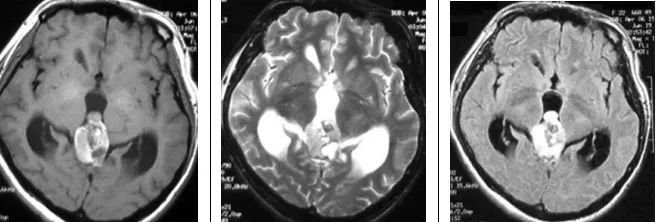

影像特征

横断位T1WI示松果体区高信号肿块,T2WI呈高信号,T21WI+FLAIR呈高信号,T1WI+C示部分强化